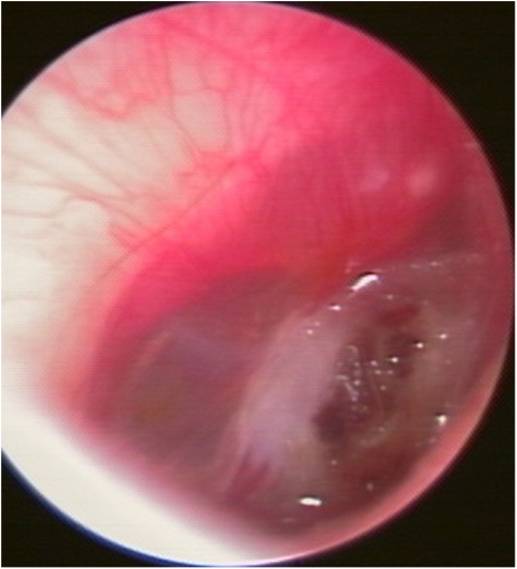

・外力により鼓膜に大きな力がかかり、鼓膜に穴が開いてしまった状態です。

・鼓膜に穴があくと難聴、耳痛、出血などが生じ、内耳障害を合併すると耳鳴、めまいなども起こします。

・穿孔が小さいものでは数週間で自然に閉じる場合もありますが、それまで正常であった耳が突然に難聴になるので、患者さんはたいそう不便を感じます。

・そのため、当科ではなるべく早く応急処置を行い、人工鼓膜で穴をふさぎます。